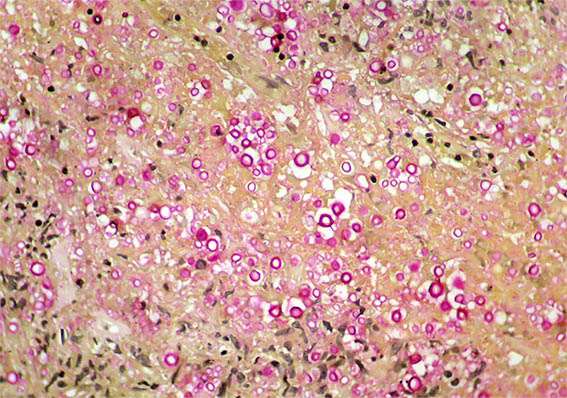

The patient is a 42-year-old man with acute kidney injury of unclear aetiology, creatinine 3.5 mg/dL, BUN: 54 mg/dL; edema in lower limbs, one week of evolution. He does not report other symptoms. As relevant history, the patient was diagnosed with HIV infection 20 days earlier and started antiretroviral therapy 2 weeks ago, which raises the possibility of acute tubulointerstitial nephritis secondary to drugs.

Look at the images of the renal biopsy:

Figure 8. Mucicarmine stain, X400.